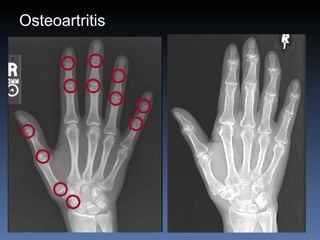

Osteoartritis IFDs, IFPs, 1 st  CMC Osteofitos Estrechez asimetrica del espacio articular  Esclerosis subcondral Quistes subcondrales No erosiones marginales Densidad osea preservada

Osteoartritis